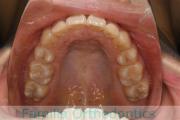

上顎

下顎